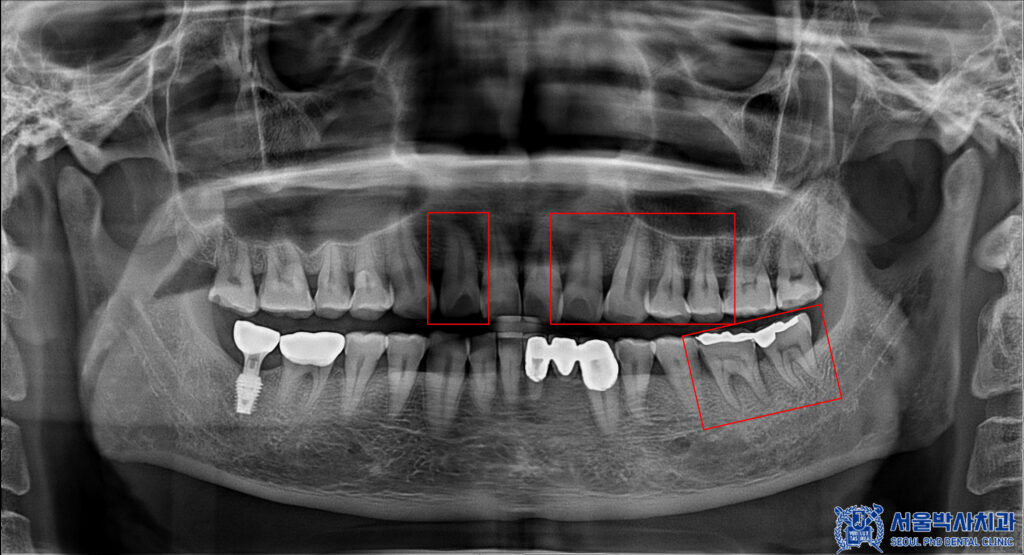

발치 전 CT를 촬영하여

잇몸과 치아 주위의 뼈 상태를

정밀히 파악한 후,

발치가 필요한 치아와 그 주변 구조에 대한

상세한 정보를 얻을 수 있었습니다.

이를 바탕으로 발치 후 임플란트를

식립할 위치와 각도를 정밀하게

계획하였습니다.

이후 임플란트를 진행한 뒤 치아는

타 치과에서 금 인레이를 진행하셨었으나

씹을 때 통증이 심한 치아 중 하나였으며,

인레이 하방으로 충치가 생겨있었습니다.